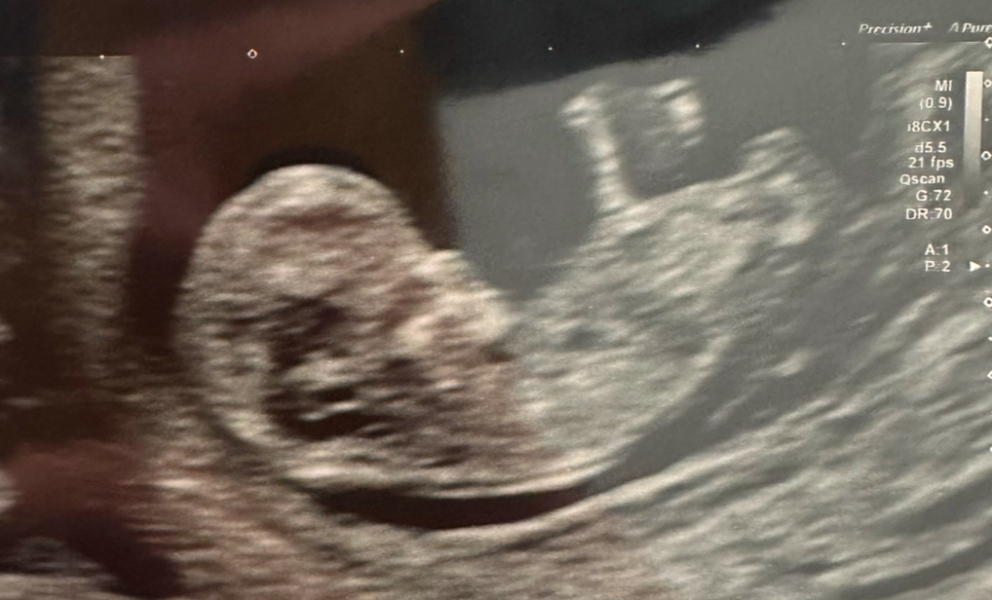

Finally had my 12 week scan today! They pushed me forward by 4 days so I will be hitting the second trimester on Friday😆

Anyone wish to hazard a guess on boy or girl? I’m thinking boy when looking at skull theory and comparing to dd’s 12 week scan.

Hope you’re all doing well

Had my 12 week scan today, they pushed me back one day so my due date is now 15/06/2025. The little one tried its best to not let them take any measurements 😂